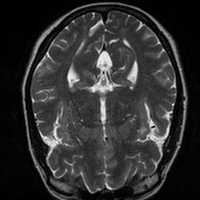

4.4 Qualitative Evaluation

In Figure 5 we analyze the prediction quality of our and compared approaches in a qualitative way. Considering modality propagation in MRI, we see that usage of uncertainty-aware patch invariance (UAPI) gives a better detailed weighting of the cerebrospinal fluid in the middle of the brain. In general, employing patch invariance yields better preservation of fine structures. This observation also applies to accelerated MRI enhancement. In particular, CUT and UAPI provide comparatively sharper knee images with more high-frequency details than the other methods.